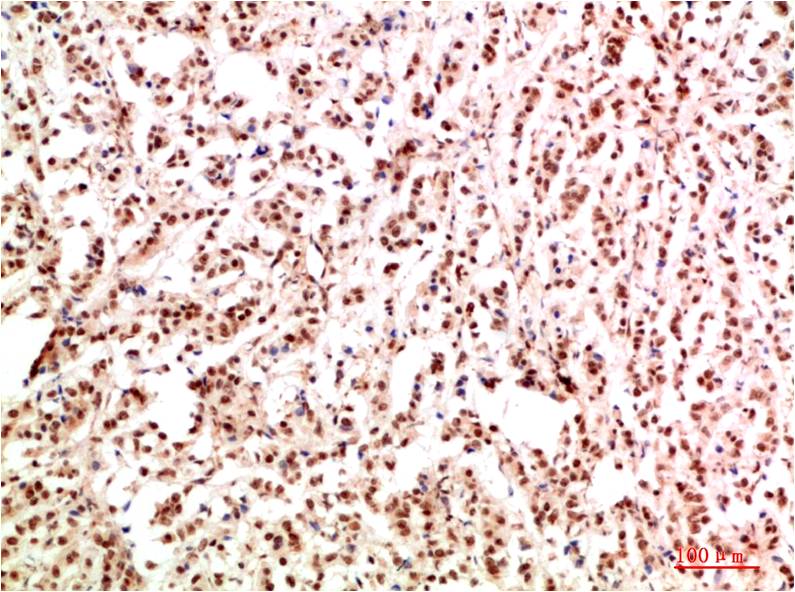

IkB α Rabbit Polyclonal Antibody

Applications :WB, IHC

| Recommended dilutions: | WB 1:500-2,000 IHC 1:50-300 |